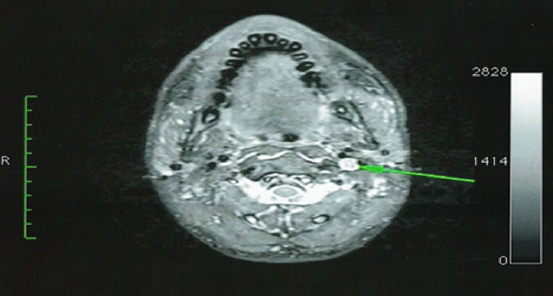

Figure 2 Axial contrast-enhanced T1-weighted Magnetic Resonance Imaging shows an avidly enhancing mass in the left carotid space.